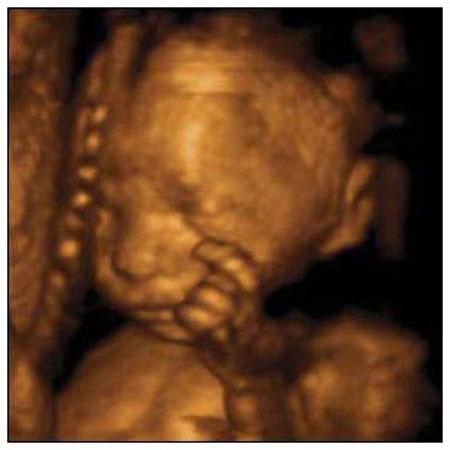

Ультразвуковые съёмки аборта на 12 неделе явно показывают: ребёнок чувствует боль, как любой из нас, и прекрасно понимает, что его хотят убить - он всеми силами старается отодвинуть от себя инструмент и широко раскрывает рот в безмолвном крике, когда у него отрывают сначала ноги, затем часть туловища…

Голову извлекают в последнюю очередь и лицо убитого ребёнка всегда искажено гримасой боли и ужаса. По этим кадрам видно, что практически нет разницы, убить ли 3-месячного ребёнка в утробе или отрезать руки -ноги -голову 5-летнему малышу. Без анестезии и в полном сознании.

- Фильм американского врача Бернарда Нэйтансона, названный «Безмолвный крик», показал всему миру, что такое аборт на сроке 11 недель беременности. Многие врачи и медсестры, посмотрев фильм, прекратили участвовать в абортах.

Это документальный фильм, и авторы рекомендуют соблюдать осторожность при его показе, поскольку некоторые кадры могут вызвать у человека психологический шок: безмолвный крик внутриутробного младенца, искаженное от боли лицо ребенка, погибающего на наших глазах...

Из закадрового текста к фильму: «Инструмент еще не коснулся ребенка, но он уже возбужден, его сердечные удары учащаются и достигают приблизительно 200 ударов в минуту. Вакуум-кюретка нащупывает ребенка, и он широко раскрывает рот в безмолвном крике».